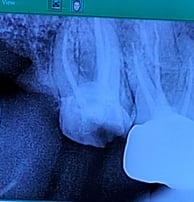

Single Sitting RCT

RCT is done in one visit, usually when the infection isn’t severe. It includes cleaning, shaping, disinfecting, and sealing the canal, followed by final restoration.